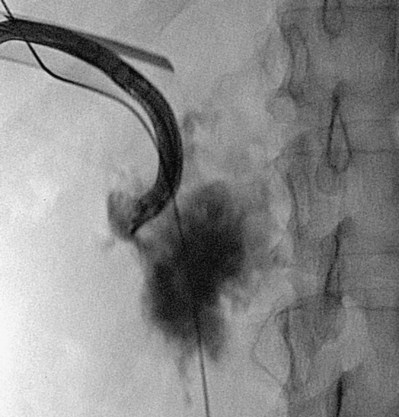

), and a guidewire can be passed from below and grasped by the nephroscope to establish through-and-through access from the external urethral meatus to the percutaneous entry site. A dual-lumen catheter can be placed as well. The small caliber of either catheter, however, does not provide much outflow from the kidney and may not prevent stone or tumor fragments from passing into the ureter along the catheter. A ureteral occlusion balloon catheter, which incorporates an approximately 15-Fr spherical balloon on the distal tip, more consistently prevents material from migrating down the ureter. The balloon should be carefully inflated in the renal pelvis, making sure the balloon is not in the ureter—which could lead to ureteral rupture—and then gently pull down to occlude the ureteropelvic junction (Fig. 47–12). Another alternative is to place a ureteral access sheath (usually 11 to 15 Fr) over a retrograde-inserted guidewire (Landman et al, 2003). The large outer diameter of the sheath effectively prevents particles from passing around the sheath into the ureter, and the large inner diameter affords excellent outflow of small stone particles. The disadvantages of employing a ureteral access sheath include the potential ureteral trauma from passing such a large device into the ureter and clogging of the catheter lumen by oversized stone fragments.

Figure 47–11 Retrogram pyelogram with air and contract reveals air in upper pole compound calyx and posterior lower pole calyx.